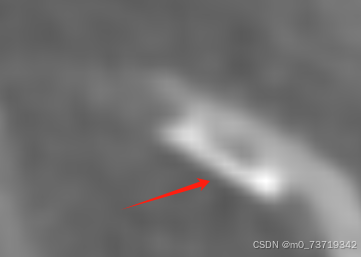

方法二:三维图像观察

血管出现明显狭窄,被侵入